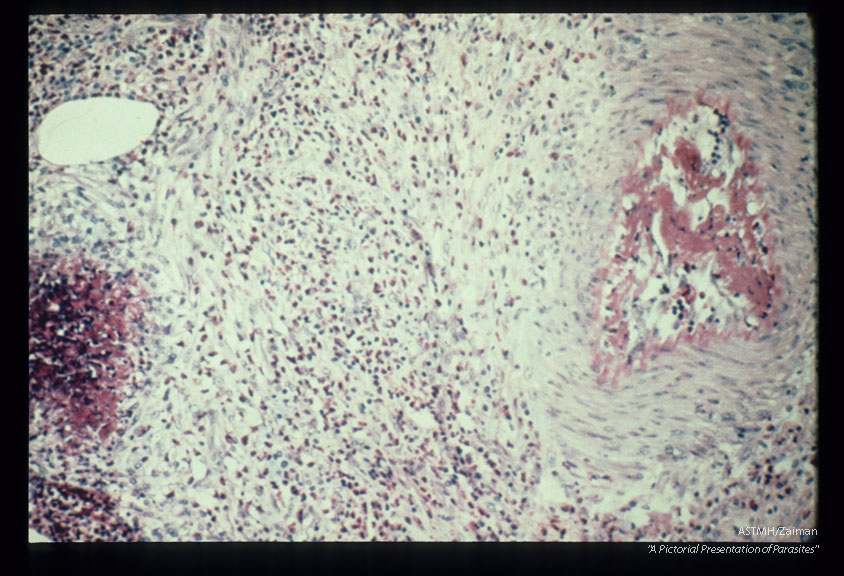

Multiple sections through anisakid nematodes and inflammatory infiltrate they induced in a human cecum.

Description: Multiple sections through anisakid nematodes and inflammatory infiltrate they induced in a human cecum.